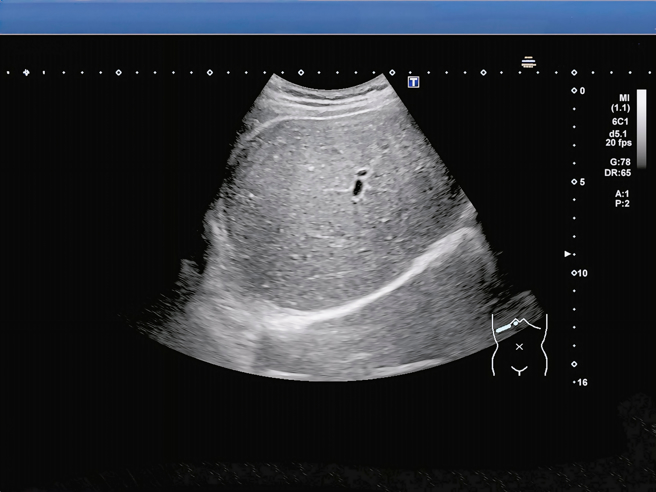

手機收購急診醫師魏智偉在《健康零距離》指出,自己遇過一名令他印象深刻的15歲高中生病患,外觀有些肥胖,因肚子劇烈疼痛送急診,檢查後確診急性胃炎,期間做超音波時更發現,他的肝「整塊白白亮亮」,有脂肪肝的問題,程度已經不是輕度。患者坦言自己每天放學後補習,都不是吃有菜有肉的便當,而是雞排配珍奶。